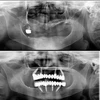

Implant tedavisi